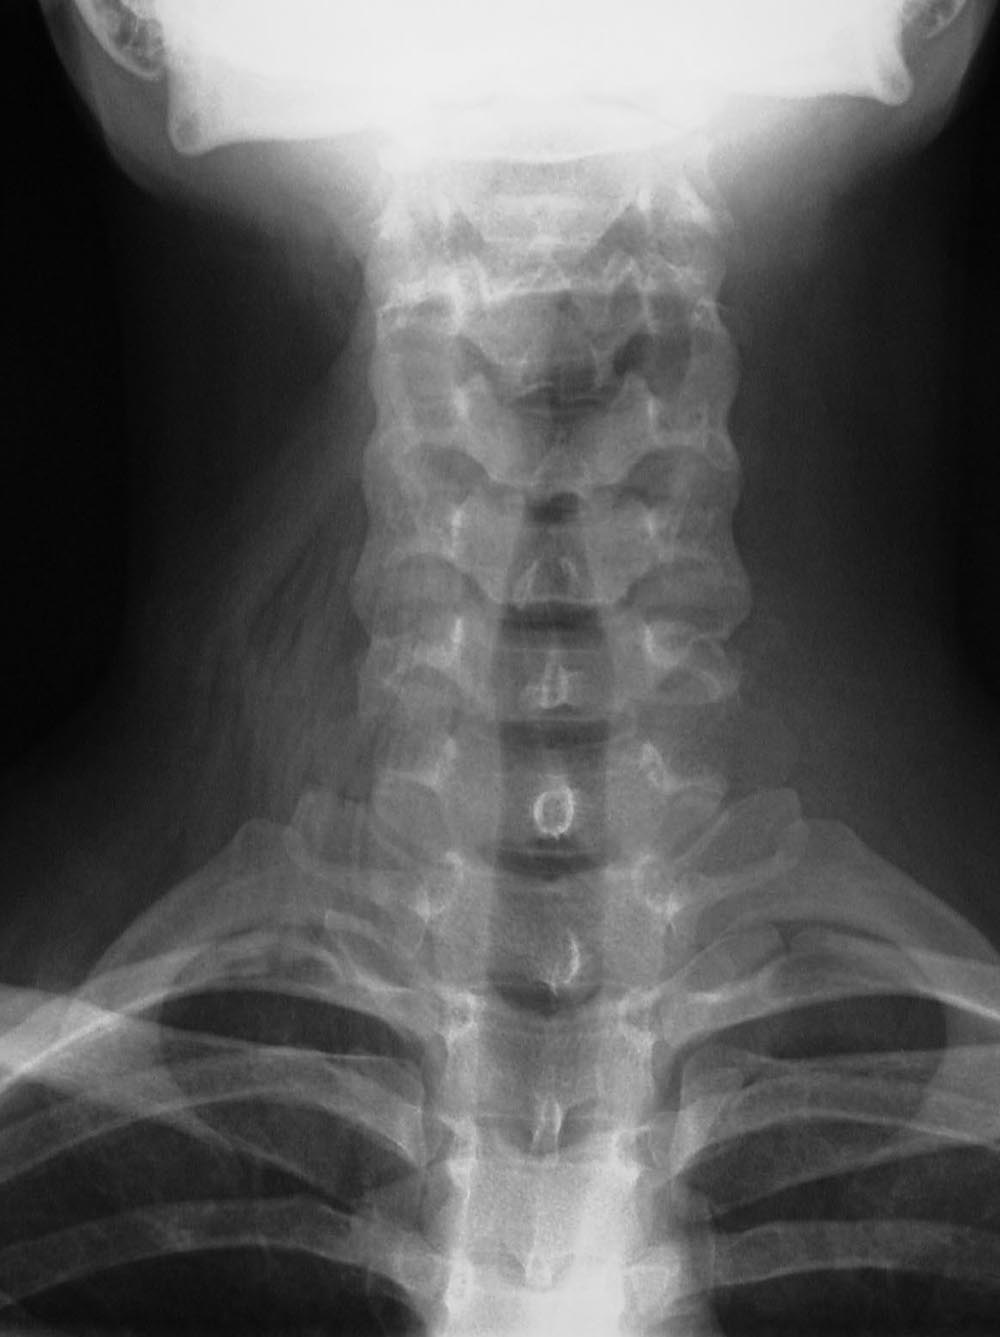

Normal everyday items carried or worn by patients - eyeglasses, earrings, hearing aids, and jewelry - may be mistaken for a medical device or foreign body; or, they may interfere with radiographic evaluation of the underlying soft tissue and bony structures. Earrings often show up on head and neck radiographs. They usually cause no confusion, but at times they can resemble electronic apparatus or even cervical spine fixation apparatus (figure: earrings). The combination of frontal and lateral views help to correctly identify earrings from medical apparatus. Even if there are frontal and lateral views, it may be difficult to distinguish unusual earrings from hearing aids.

Dental and facial apparatus often is present on cervical spine radiographs and should be evaluated as best as possible even though its evaluation was not the original intent of the imaging study. It is not all that uncommon for important maxillary, mandibular, or dental disease to be incidentally noted on routine imaging of the head, neck, or cervical spine.